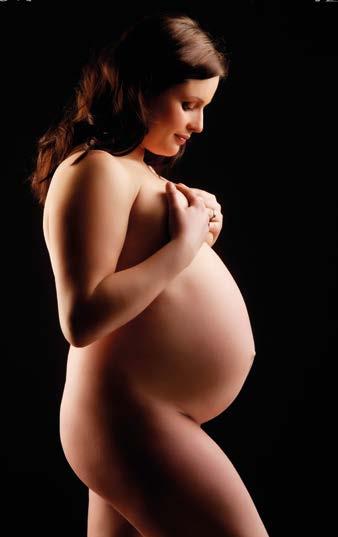

S blížícím se koncem těhotenství se zcela přirozeně u většiny žen i ostatních rodinných příslušníků zvyšuje netrpělivost. Obvykle se zde střetávají dva momenty. Na straně jedné je to obava ze samotného porodu a z faktu příchodu nového člena do rodiny, na straně druhé nedočkavost a touha po tom, aby nastávající maminka své dítě již mohla držet v náručí. Z toho vyplývá naprosto pochopitelný stav určité nervozity smíšený s jistou dávkou vzrušení z očekávání příchodu nového člena rodiny.

Tato část těhotenství, která začíná završením 13. týdne a končí ve 26. týdnu, je pro velkou část žen tím nejkrásnějším obdobím. V těchto měsících se mnoho žen cítí opět v dobré duševní i fyzické pohodě. Nevolnosti a únava ustoupily a bříško, které se již stává patrné pro okolí, nebývá

Třetí trimestr těhotenství je období od 27. týdne těhotenství do porodu. S blížícím se koncem těhotenství se zcela přirozeně zvyšuje netrpělivost většiny nastávajících maminek i jejich okolí. Roste obava z porodu samého a z faktu, že žena bude mít dítě. Zároveň se ale stupňuje nedočkavost a touha po tom, aby maminka své dítě již mohla držet v náručí.